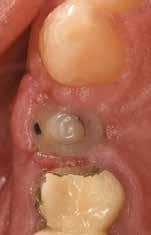

Egy fiatal páciens jelentkezett nálunk, akinek eltörött a szabad véggel rendelkező hídja (1. ábra). A hiányzó, első premoláris fog esetén implantációs pótlást javasoltunk. A csontállomány értékeléséhez CBCT-vizsgálatot végeztünk, és az elemzéséhez NNT Viewert (NewTom) használtunk, és copaSKY 4×10 mm-es (bredent medical) implantátumot választottuk a fog pótlásához

1. ábra: Műtét előtti fogászati panorámafelvétel, amelyen a hiányzó felső állcsont jobb első premolárisát és a szabad véggel rendelkező hidat láthatjuk. — 2. ábra: Az implantátum méreteinek megtervezése CBCT-vel. 3. ábra: Bukkális lágyrészdefektus. — 4. ábra: A biológiai szélesség értékelése a vertikális lágyszövetvastagság alapján. 5. ábra: Palatinális „tekercslebeny” – Palatal roll flap. — 6. ábra: Bredent medical copaSKY 4x10 implantátumbeültetés. 7. ábra: Szubkresztális implantátumbeültetés a várható biológiai szélességnek megfelelően.

(2. ábra). A lágyszövetek értékelése Seibert szerinti I. osztályú csontdefektust állapított meg (3. ábra), ezért a beavatkozáskor palatinális „tekercslebenyt” preparáltunk (palatal roll flap), és implantációt végeztünk, hogy kompenzálni tudjuk a bukkális lágyszövet-behúzódást. Megmértük a vertikális lágyszövetvastagságot, és úgy terveztük, hogy a szubkresztális implantátum beültetése összhangban legyen a biológiai szélesség kialakulásával a transzgingivális gyógyulási periódus alatt (4. ábra)